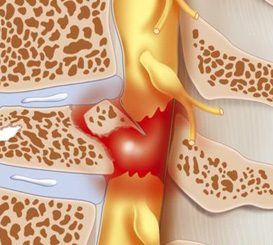

Dr. Yash Shah is one of the very few National Board certified, Degree [FNB(Spine)] honored Spine specialist is recognized amongst the best spine surgeons of our country. He heads the Mumbai Spine Clinic, a premium health care provider for patients suffering from Back Pain, neck pain, Spondylosis, Slip disc, Disc herniation, Spinal Stenosis, Spine TB, Scoliosis and Kyphosis or spine deformity.

A Conservative(non-surgical) treatment is tried initially for most patients as most of our patients improve with the same. Surgery is offered when absolutely indicated and proven to give better results and are done with latest technologies at some of the best hospitals in Mumbai with well- equipped operation theatres.

Understanding Endoscopic Spine Surgery: A Minimally Invasive Solution for Back Pain